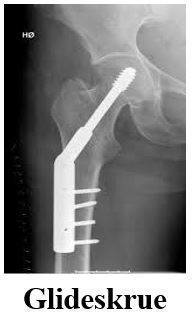

Der findes 3 forskellige typer hoftebrud. Vi har sat kryds ved den type brud du har.

Bruddet på- eller under lårbensknuden samles med en glideskrue eller et marvsøm og skruer. I sjældne tilfælde anvendes en anden operationsmetode.

Behandling af dit brud afhænger af bruddets type.

Der er i dit tilfælde anvendt den operationsform, som er afkrydset, se billeder på næste side. Forskellige brud i hoften behandles med skruer, med halvprotese, med glideskrue, med et marvsøm og skruer.